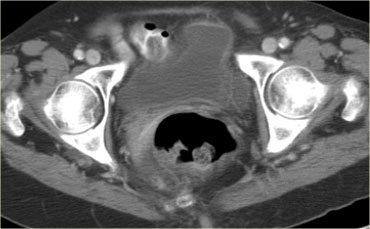

Di căn dạng nang đến buồng trứng

Mặc dù di căn đến buồng trứng thường có dạng đặc – chẳng hạn như di căn Krukenberg – di căn buồng trứng dạng nang vẫn có thể xảy ra.

Hình CT cho thấy các khối nang phức tạp ở cả hai buồng trứng.

Mặc dù ung thư biểu mô tuyến nang thanh dịch có thể xuất hiện hai bên, nhưng loại này thường có dạng đơn thùy hơn là đa thùy.

Hầu như không nhìn thấy một phần của ung thư đại trực tràng dạng vòng nhẫn (mũi tên xanh).

Nhìn thấy rõ ràng là các tổn thương cấy ghép dạng nang trên phúc mạc phản chiếu (mũi tên đỏ).

Đây là các tổn thương di căn buồng trứng dạng nang của ung thư đại trực tràng.

Đây là một đặc điểm hình ảnh không thường gặp.